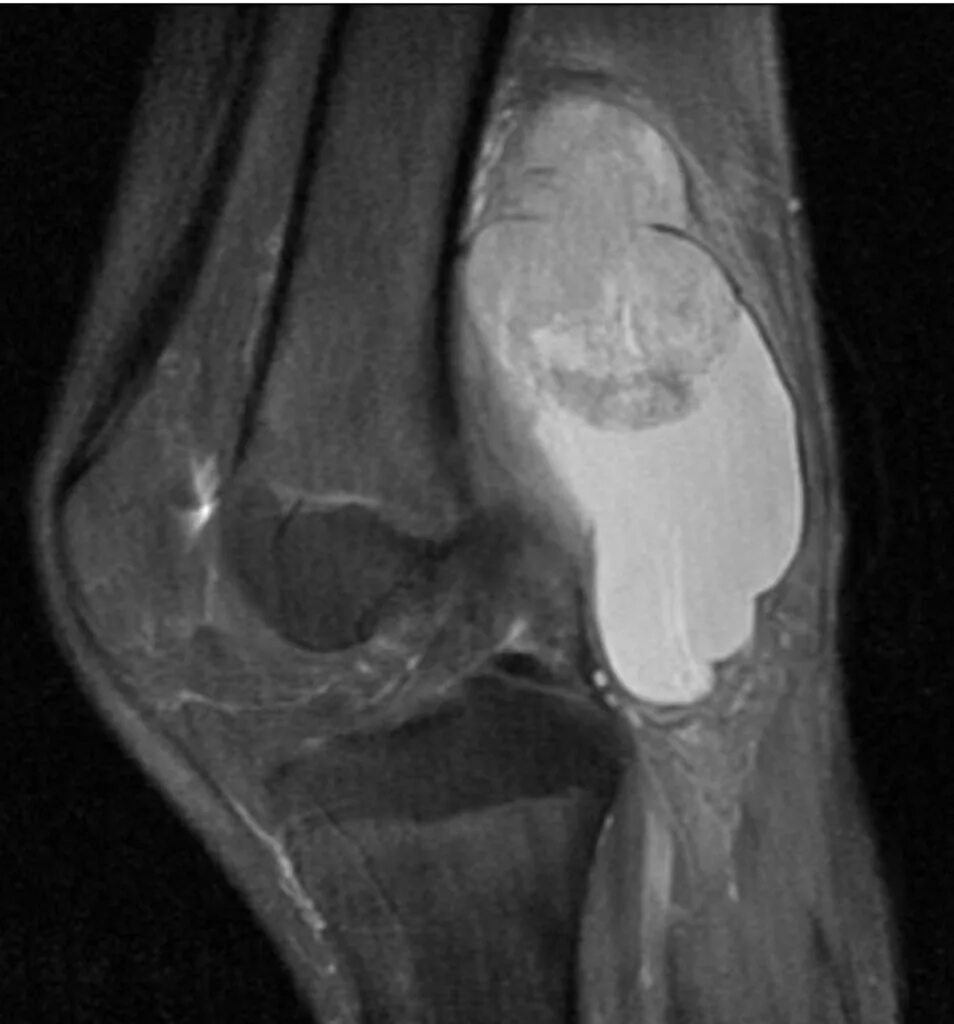

Саркома мрт